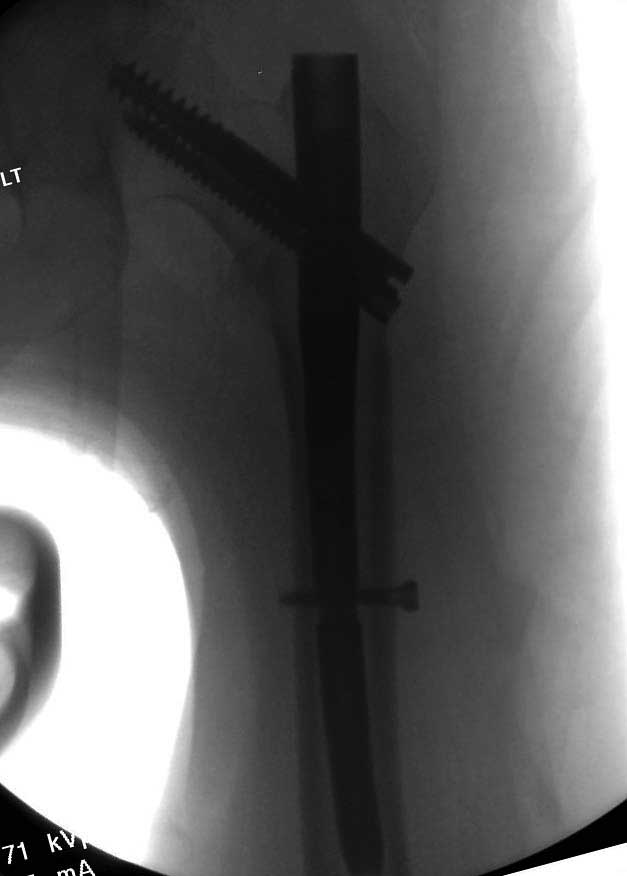

Повторно поступает после двух с половиной лет, где обнаруживается перелом на второй стороне. Немного сложно, но для фиксации выбрали Antegrade InterTan Smith Nephew Nail и с момента фиксации более 3х мес.

Имя     : 33 IT fx LT injury CRM2.JPG

Тип     : image/jpg

Размер  : 28908 байтов

Описание: отсутствует

Url     : http://weborto.net:8080/pipermail/ortho/attachments/20120510/52aada75/attachment-0053.jpg